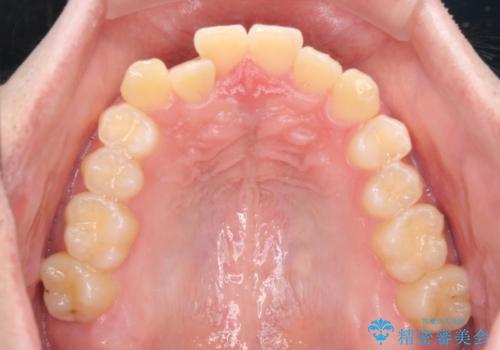

- 前歯のクロスバイトを気にして来院された患者様です。

骨格的には問題がなかったため、インビザラインを用いて咬み合わせを改善していくこととしました。

インビザライン特有の、奥歯の咬み合わせの問題もなく、しっかりと歯列を改善することができました。

舌側転位している上顎側切歯(内側に引っ込んでいる真ん中から2番目の歯)は、インビザラインが最も移動を苦手とする歯であり、これ以上の改善を望まれる場合にはワイヤー矯正、あるいはワイヤー矯正の併用をお勧めいたします。